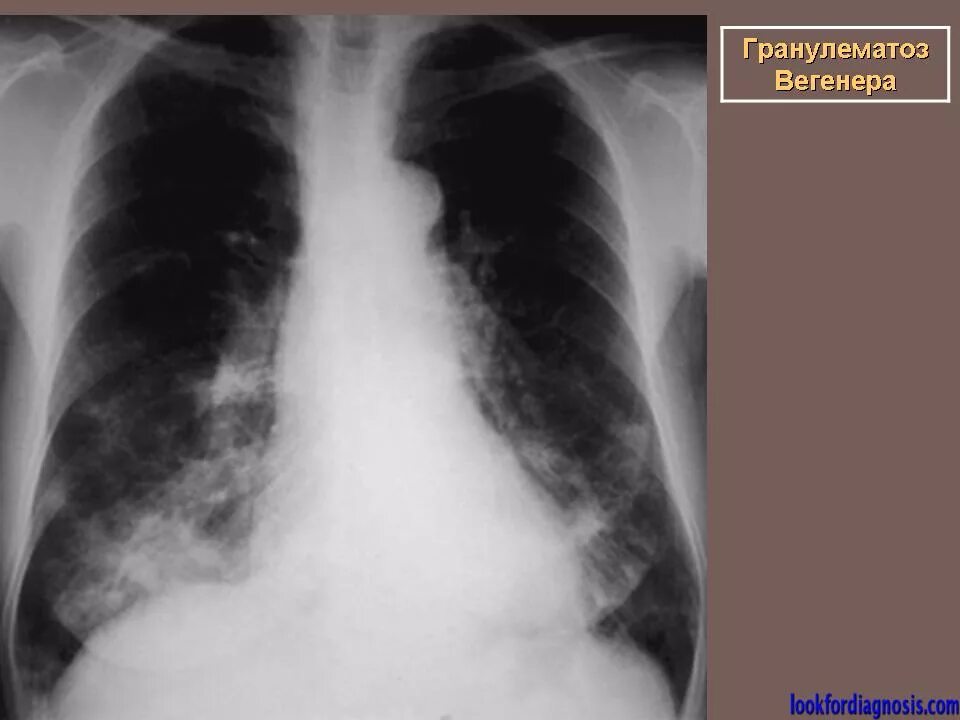

Гранулематоз лечение